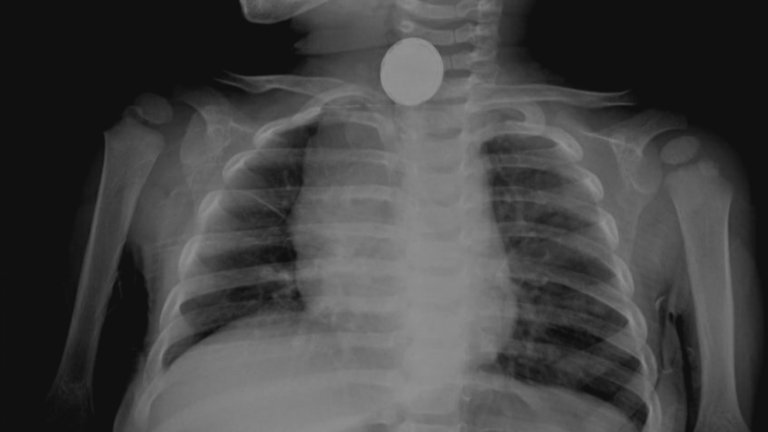

И това съвсем не е безобидно. Самият лекар е имал случай с момче на 10 години, което е било със запушени носни проходи и е изпитвало сериозна болка. Оказало се, че причината е заседнала батерия.

Хората са глътнали с или без да искат нож за пържоли, фенерче, сим карта, играчки, монети - един от пациентите дори хвърлил три във въздуха и ги поел с уста, след което ги глътнал, цигари, алуминиево фолио (в което било увито бурито, но човекът забравил да го махне и изял всичко), шноли за коса, ключове, кучешки и котешки играчки и дори стрелички за дартс.